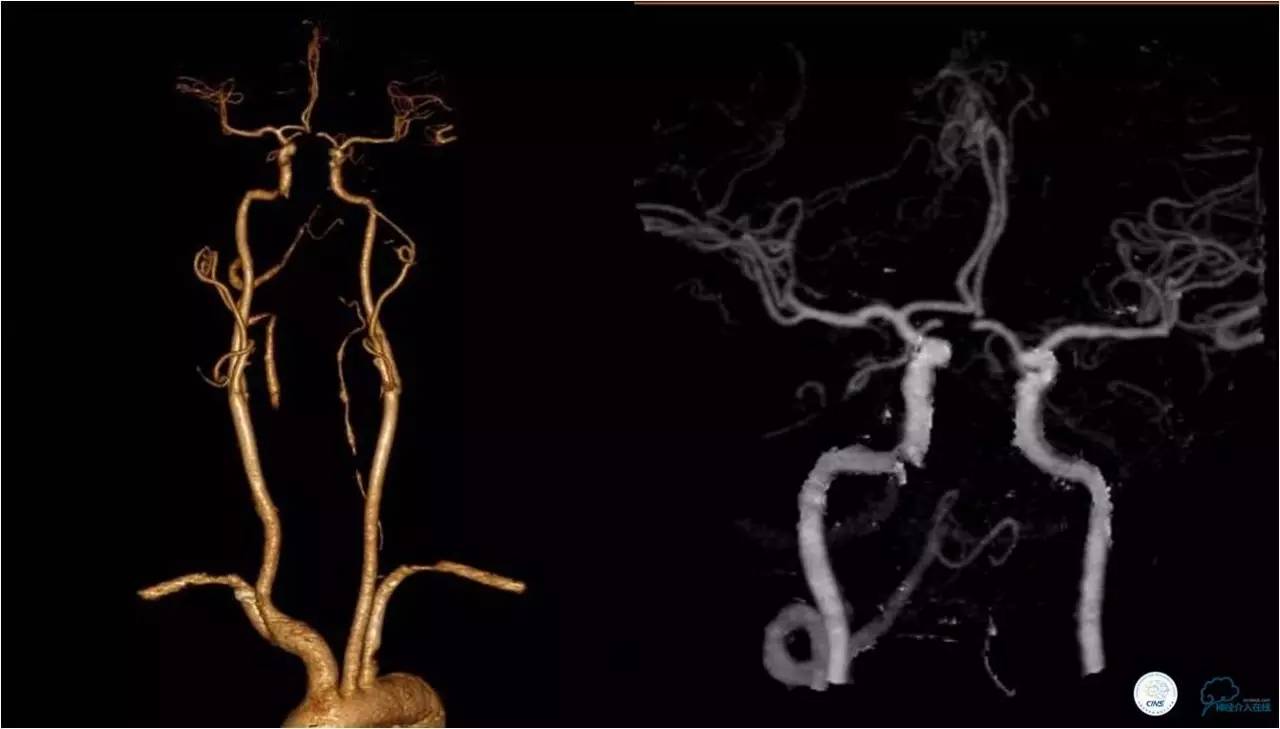

》急诊CTA:基底动脉闭塞,右侧椎动脉起始端长段闭塞。

》术前急诊CTA

★右侧椎动脉起始端长段闭塞,右侧颈深动脉向右侧椎动脉供血,远端基底动脉不显影;左侧椎动脉纤细,V3段以远不显影。

★右侧颈总动脉正侧位,可见右侧枕动脉通过肌支向右侧椎动脉供血,远端基底动脉不显影。